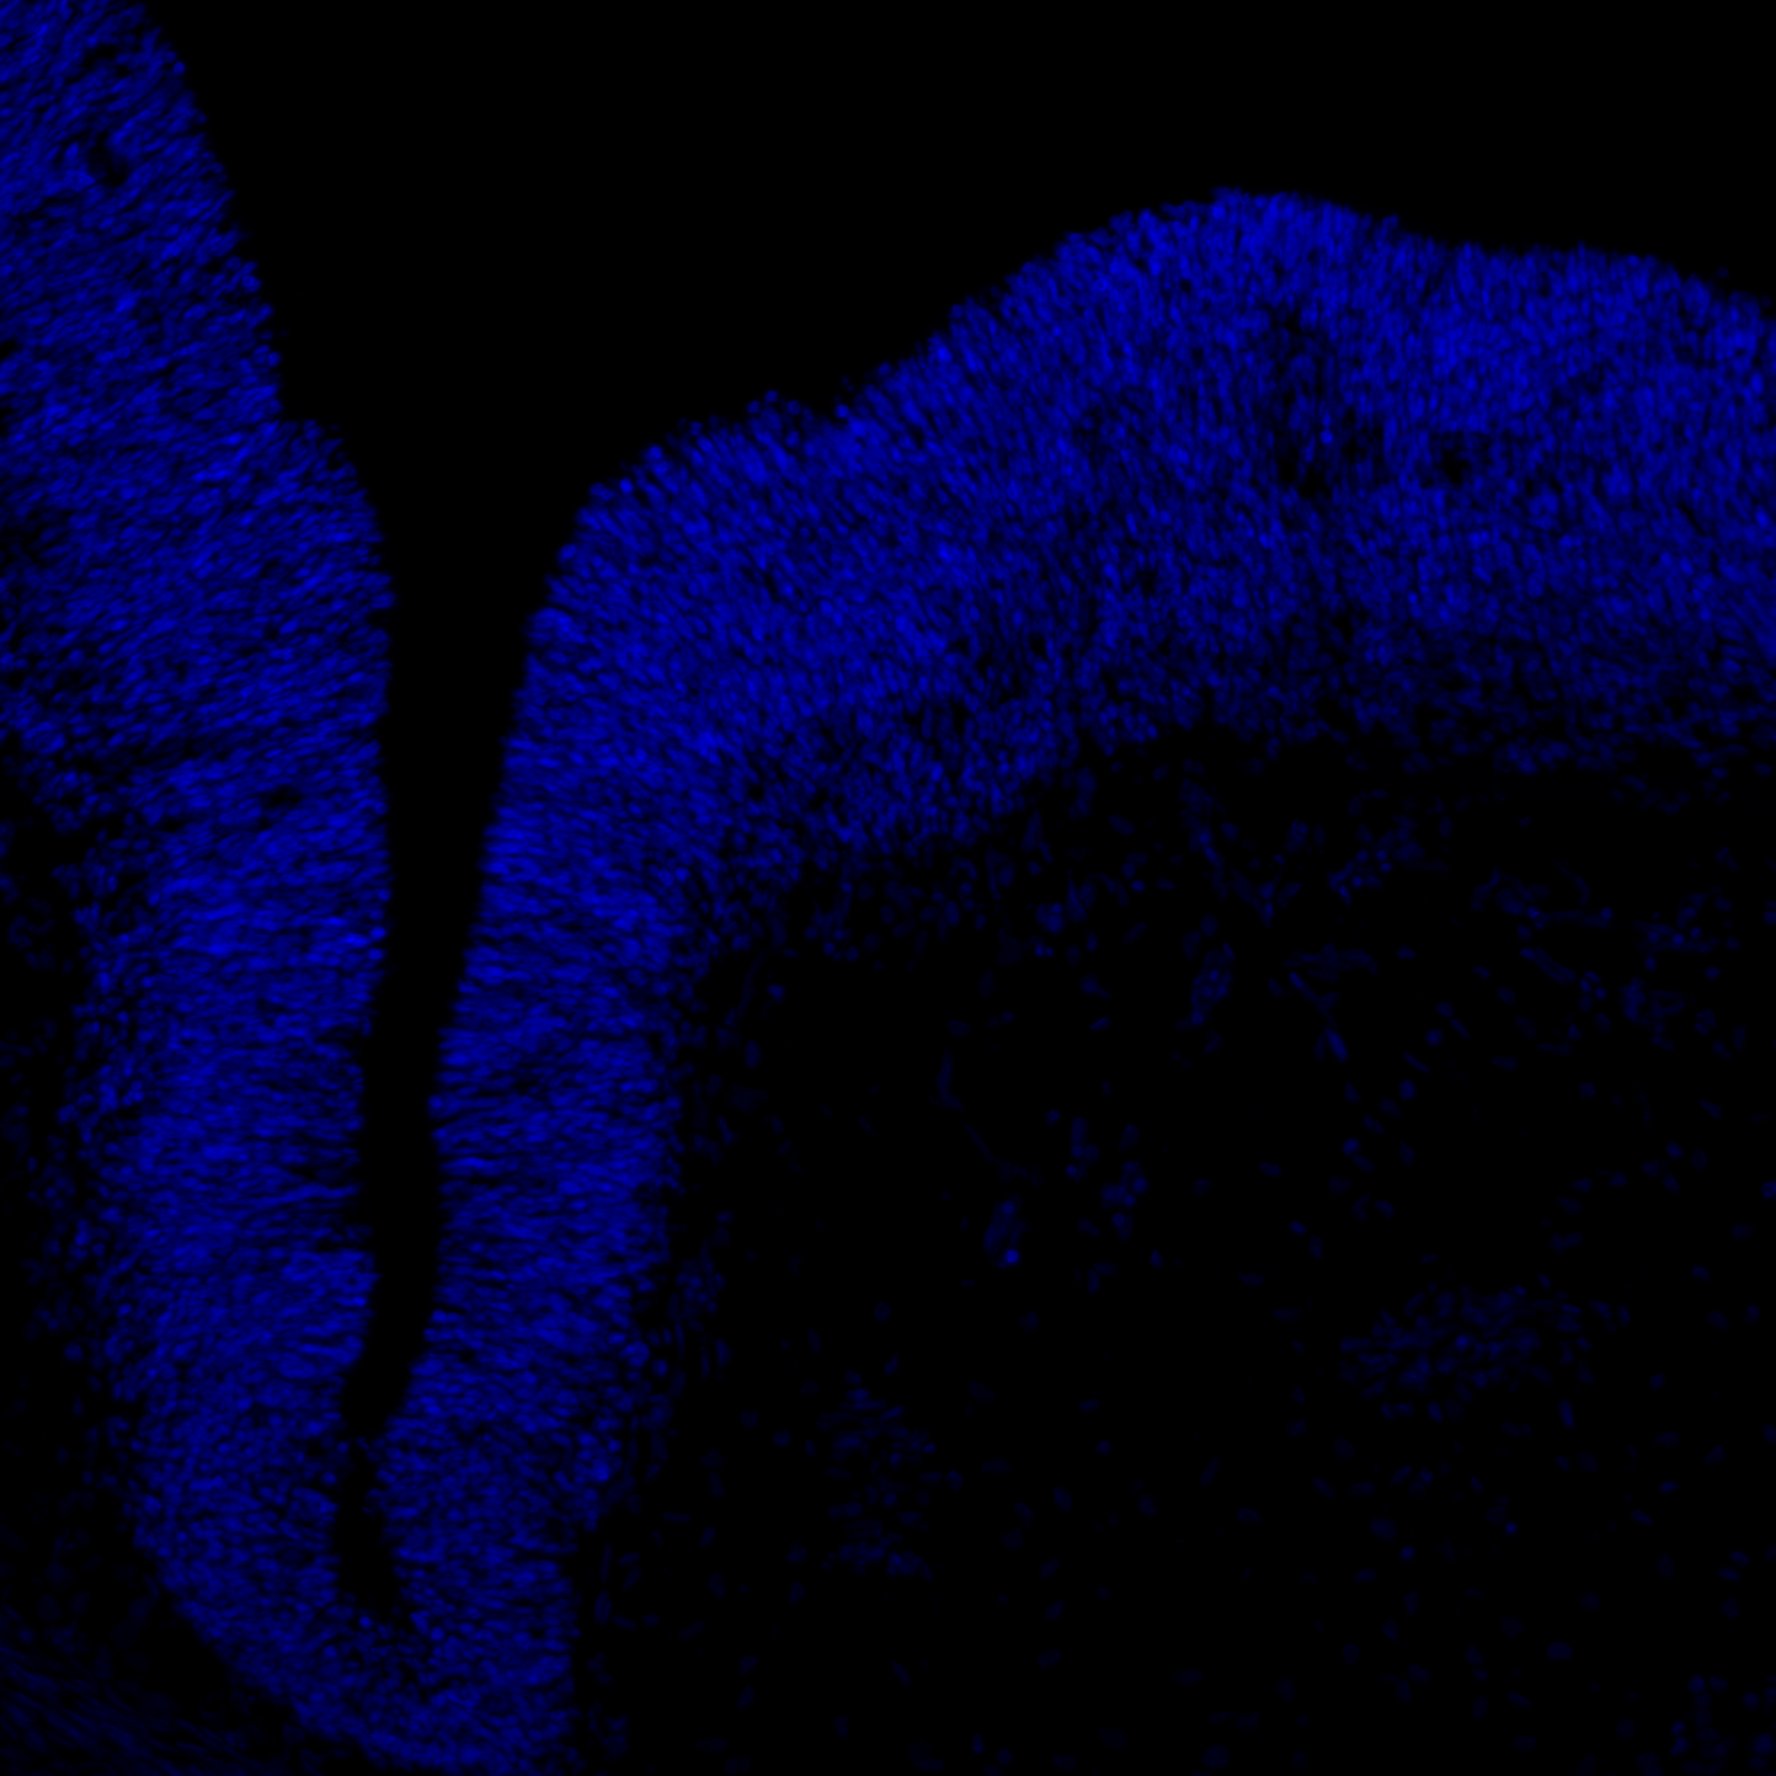

DAPI

6PCW human midbrain